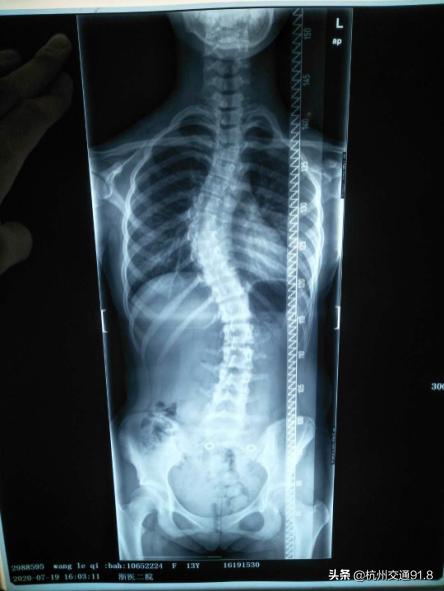

无独有偶,浙大医学院附属市一医院针灸推拿科最近也来了一个13岁的小姑娘,和晨晨可谓“难姐难妹”。爸妈也是无意间发现她总是斜着身子走路,结果来医院一查,发现脊柱侧弯已经成了“S”型。

病例X光照片

针灸推拿科主治医师张狄介绍,脊柱侧弯后,脊椎骨的位置弯曲旋转,使附着于其上的肌肉牵拉移位,从而使脊柱两侧的肌肉不平衡。张狄医师先用推拿手法放松两侧的肌肉,然后用整脊手法调整脊柱的位置。